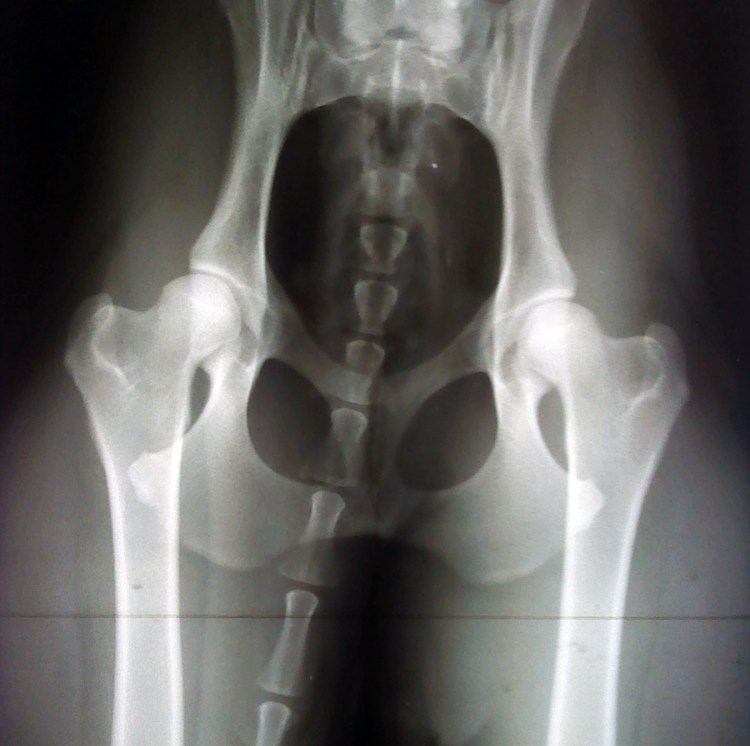

Hade blivit tipsad av Eva K att åka just dit för att de är kända för att ta bra bilder. De var verkligen proffsiga – det hela gick snabbt och smidigt. Lugnande, upp på bordet och *snapp*. Snart hängde plåtarna på väggen och resultatet kan ni se nedan 😀 :

Alltid lika spännande med höftledsröntgen – men bilden ser fin ut!